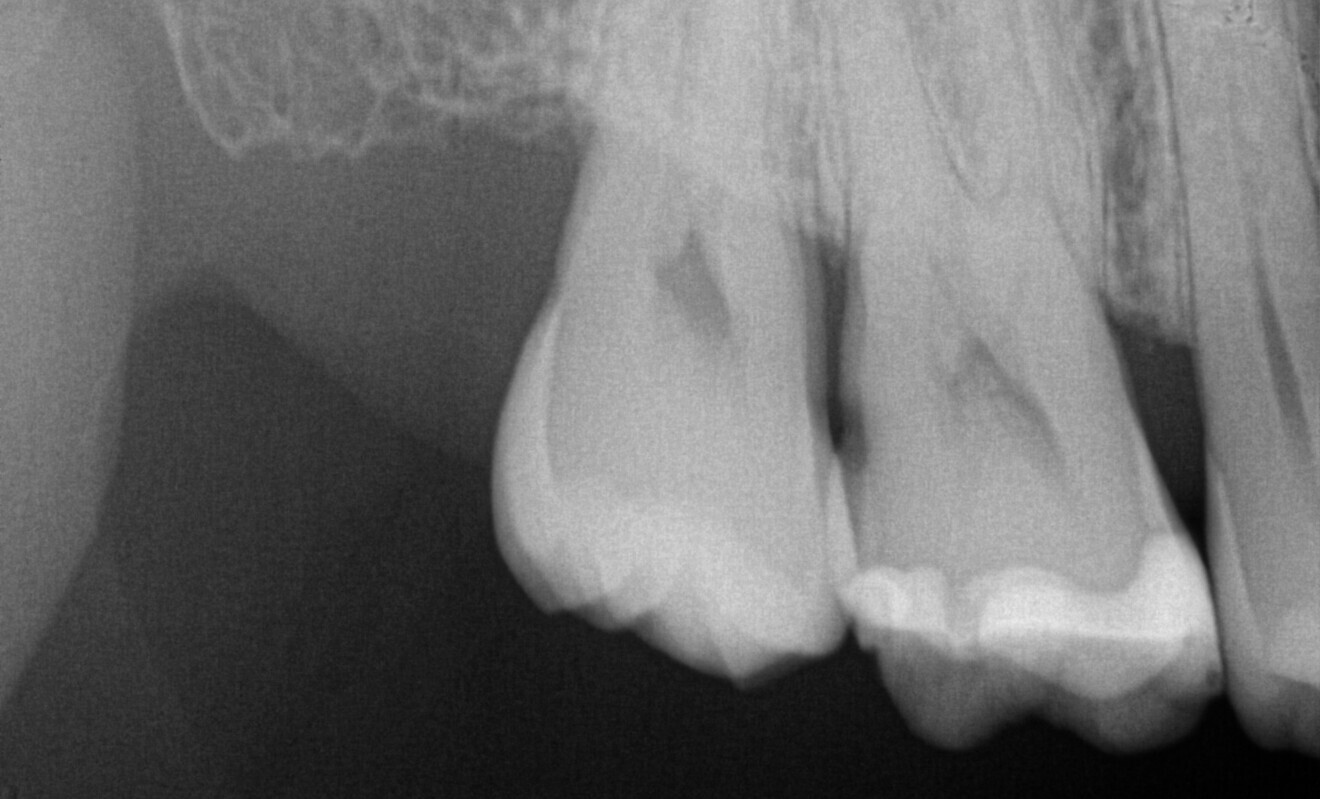

Fig. 20: Bitewing radiograph of the existing composite restorations.

A 23-year-old female patient presented with cold sensitivity of the teeth in the maxillary right posterior sextant. Examination noted old composite fillings in the molars and premolars and recurrent caries on each tooth (Fig. 19). A bitewing radiograph was taken to evaluate the extent of the recurrent caries and the dimensions of the composite restorations (Fig. 20). Owing to the dimensions of the restorations and caries, inlay and onlay restorations were suggested to restore the teeth and preserve tooth structure as an alternative to complete crowns. The patient’s questions were answered, and she agreed to the proposed treatment. She was informed that the treatment could be completed in a single appointment utilising 3D printing for restoration fabrication. Time in the schedule permitted treatment to be performed during that same appointment. Our intent is to provide conservative restoration with superior accuracy and definition compared with milling, as well as better predictability and mechanical properties compared with direct resin composite restorations.